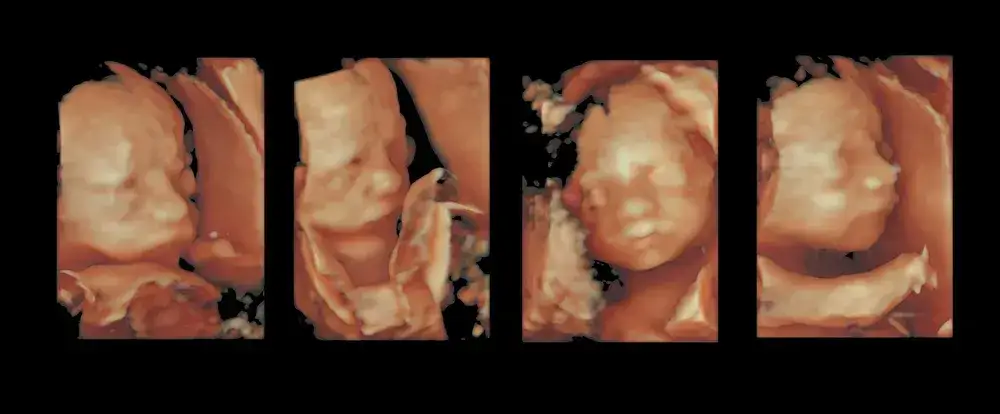

Czas na USG III trymestru: Co sprawdzi lekarz podczas badania?

Między 28. a 32. tygodniem ciąży zazwyczaj wykonuje się USG III trymestru. To bardzo ważne badanie, podczas którego lekarz oceni:

- Masę płodu i tempo jego wzrostu.

- Ułożenie dziecka (główkowe, pośladkowe, poprzeczne).

- Ilość wód płodowych, co jest wskaźnikiem dobrostanu maluszka.

- Wydolność łożyska i jego lokalizację.

- Przepływy krwi w naczyniach dziecka i macicy.

To badanie dostarcza kluczowych informacji, które mogą wpłynąć na planowanie dalszej opieki i przebiegu porodu.